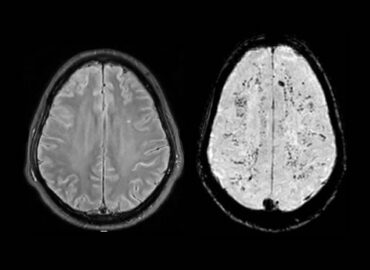

Mujer de 30 años sin antecedentes patológicos ni hábitos tóxicos es derivada del interior de la provincia de Córdoba por […]